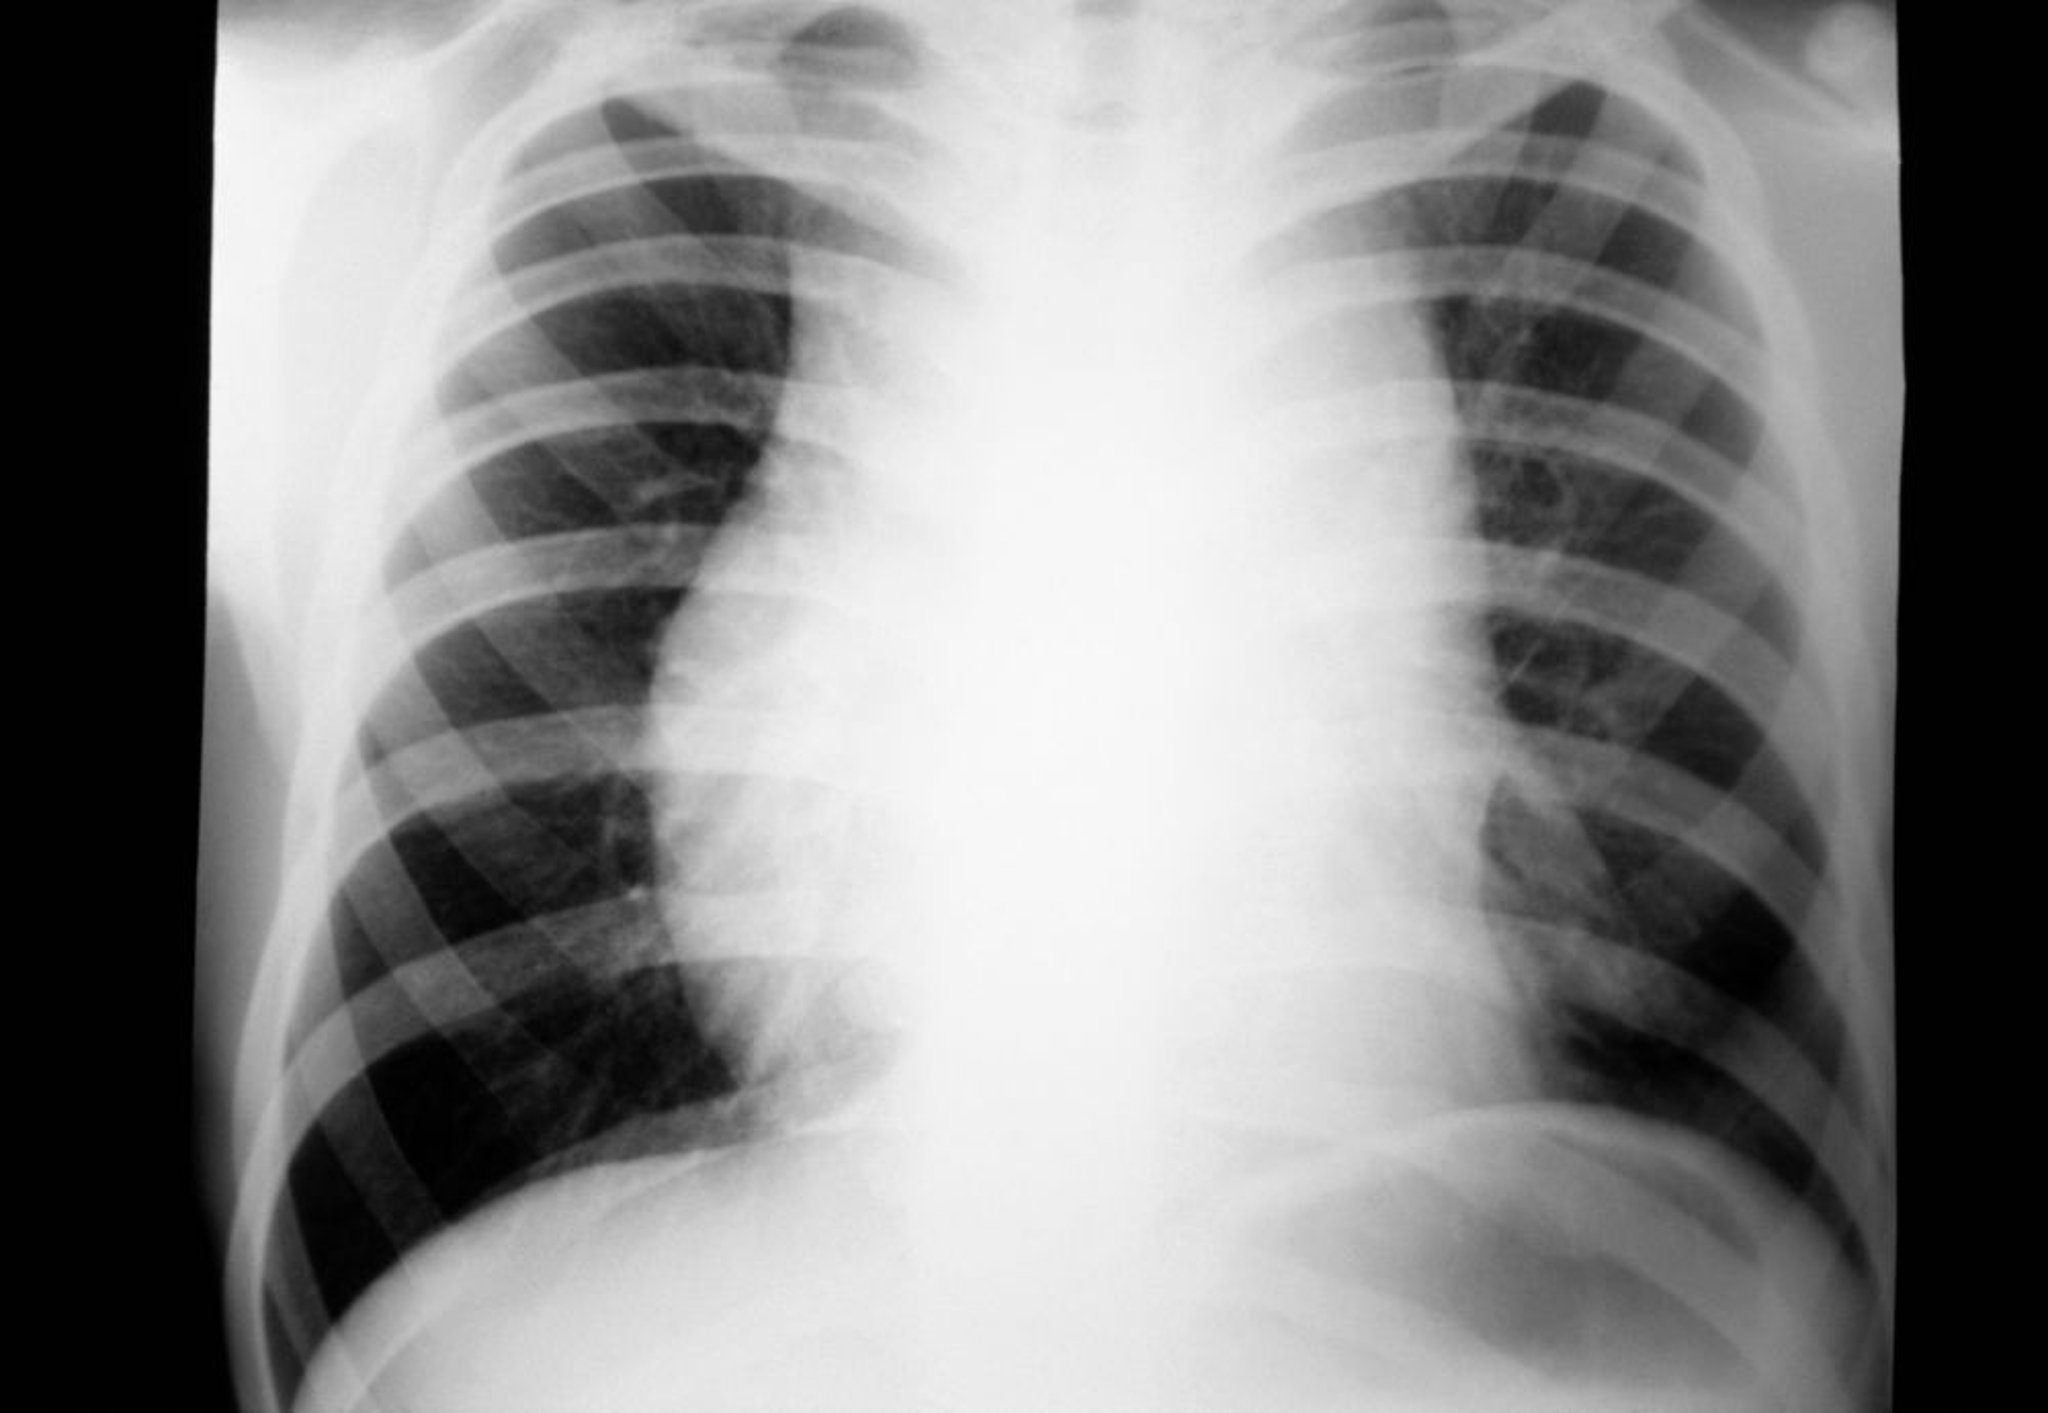

U lympho Hodgkin (nổi hạch trung thất)

Phim X quang ngực của một bệnh nhân mắc u lympho Hodgkin cho thấy hạch to ở trung thất.